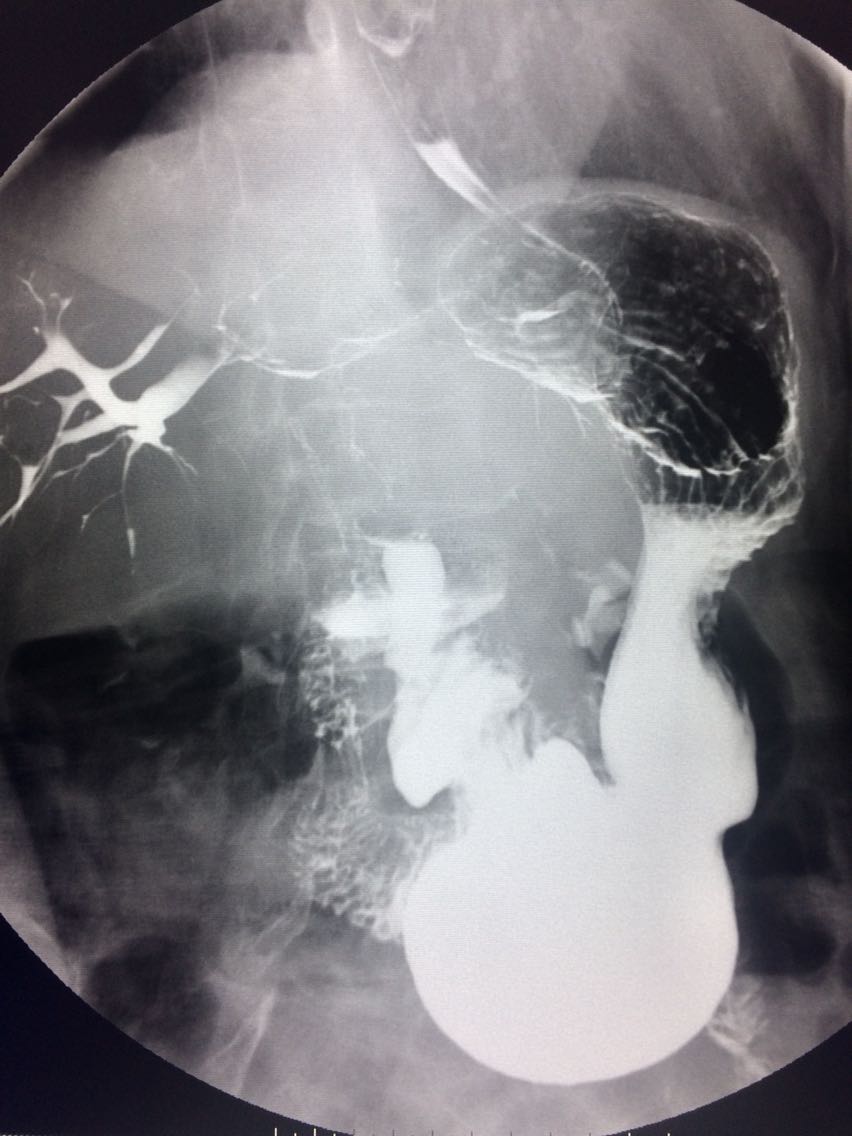

查体未见明显异常。 上消化道造影如图。

诊断食管癌。 造影剂逆流入胆道。

讨论食管癌的分型? 造影剂逆流的原因及处理方法?